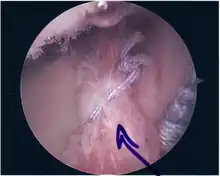

Surgical treatment of SLAP tears has become more common in recent years. The success rate for repairing isolated SLAP tears is reported between 74-94%.[8] While surgery can be performed as a traditional open procedure, an arthroscopic technique[9] is currently favored being less intrusive with low chance of iatrogenic infection.[10]

Following inspection and determination of the extent of injury, the basic labrum repair is as follows.

- The glenoid and labrum are roughened to increase contact surface area and promote re-growth.

- Locations for the bone anchors are selected based on number and severity of tear. A severe tear involving both SLAP and Bankart lesions may require seven anchors. Simple tears may only require one.

- The glenoid is drilled for the anchor implantation.

- Anchors are inserted in the glenoid.

- The suture component of the implant is tied through the labrum and knotted such that the labrum is in tight contact with the glenoid surface.